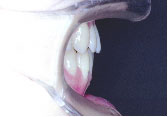

下の歯が上の歯より前に出て前歯は咬めていません。左上の第2小臼歯は骨の中に埋まっています。

また下あごは左にずれています。顎変形症、下顎前突と診断しました。